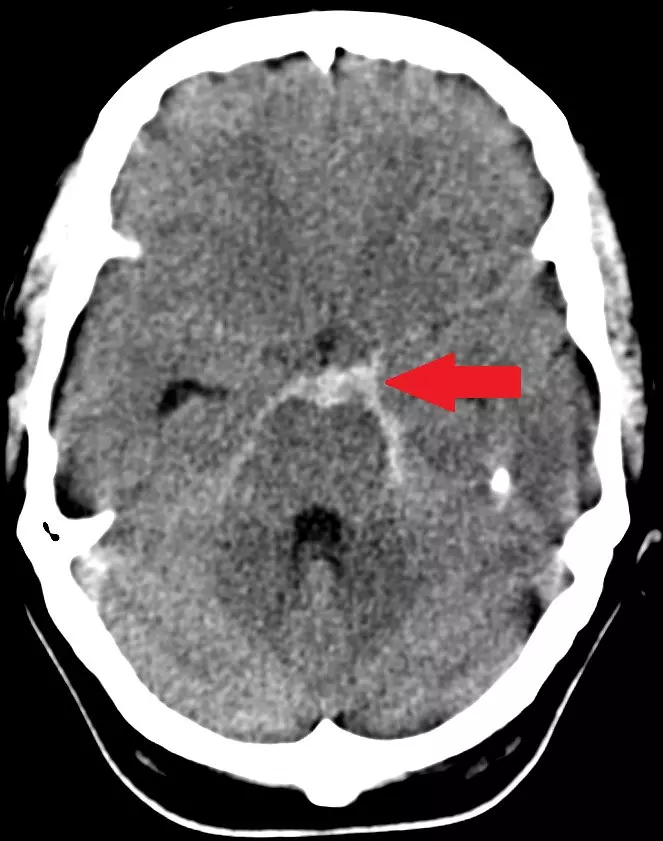

Patients presenting with a suspected SAH should always have an urgent CT scan of the head, without contrast. This helps to identify the presence of subarachnoid blood, which will guide any following management. A positive result is seen when there is an area of increased density around the Circle of Willis, depicting blood in the basal cisterns.

Image - A CT slice of the human brain. In the centre, there are hyper-dense (brighter) areas corresponding to blood in the subarachnoid basal cisterns (area highlighted by red arrow)

Creative commons source by Lipothymia [CC BY-SA 4.0 (https://creativecommons.org/licenses/by-sa/4.0)]